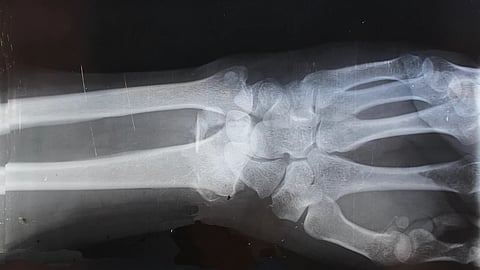

Loss of Grip Strength:

A decrease in grip strength may be a subtle sign of weakening bones in the hands and wrists. While it can be attributed to various factors, such as ageing and muscle weakness, it's essential to consider bone health as a potential contributor. Exercises that target hand and wrist strength can aid in maintaining bone density in these areas.